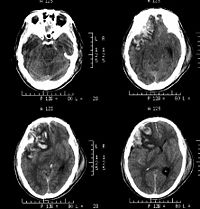

右侧颞叶脑挫裂伤

,区别只在于何者为重或何者为轻的问题。通常脑表面的挫裂伤多在暴力打击的部位和对冲的部位,尤其是后者,总是较为严重并常以额、颞前端和底部为多,这是由于脑组织在颅腔内的滑动及碰撞所引起的。脑实质内的挫裂伤,则常因脑组织的变形和剪性应力引起损伤,往往见于不同介质的结构之间,并以挫伤及点状出血为主。

CT扫描

对脑挫裂伤与脑震荡可以作出明确的鉴别诊断,并能清楚地显示脑挫裂伤的部位、程度和有无继发损害,如出血和水肿情况。同时,可根据脑室和脑池的大小、形态和移位的情况间接估计颅内压的高低。尤为重要的是,对一些不典型的病例,可以通过定期CT扫描,动态地观察脑水肿的演变或迟发性血肿的发生。近年来,在有此设备的医院CT已作为急性头伤的常规检查,因为单靠伤史和查体难以作出超早期诊断。Stein等(1990)指出在GCS13~15危害较小的轻型头

伤中,首次CT的阳性发现率竟占18%,并有5%需行手术治疗,强调早期CT检查的必要性。